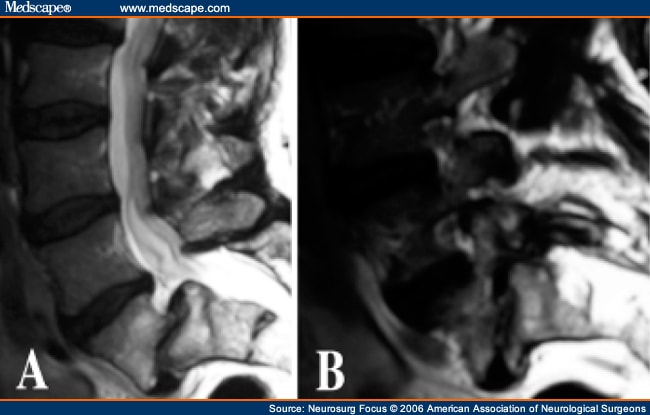

Acquired Degenerative Changes Of The Intervertebral Segments ...

These findings indicate that the posterior elements are major locations of degenerative spinal and perispinal disease Normal sagittal appearance of the L4-L5 and L5-S1 neural foramen collision and sclerosis of the apex of the superior articular process of L5 and the overlying pars ... Access Full Source